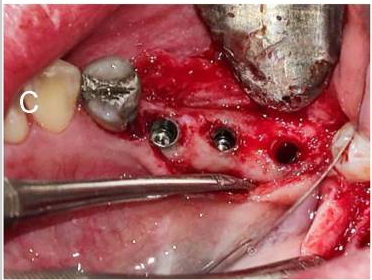

(A) Soft tissue thickness measurement (B) Keratinized gingiva measurement (C) Implant placement (D) Three months after implant placement and healing abutment closure